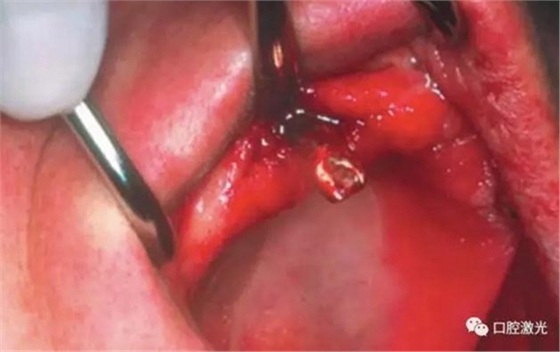

對患者實施局部麻醉,隨后在種植體位置進行翻瓣。利用塑料刮治器將肉芽組織清除干凈,并將翻瓣邊緣削薄。此時在種植體周圍可見明顯骨缺失。

半導體激光滅菌

利用半導體激光照射已經(jīng)暴露的種植體表面。激光輸出功率1.0W,連續(xù)模式,照射時間20秒,光纖芯徑400um,光纖尖不初始化。由于激光的選擇性吸收的特點,該激光能量設(shè)定足以殺滅導致種植體周圍炎的厭氧菌,卻不會對種植體表面和種植體周圍生物組織(骨組織、黏膜組織)造成熱或者機械損害。在軟組織恢復6周和12周后分別再進行一次激光滅菌治療(參照牙周炎激光滅菌程序)。